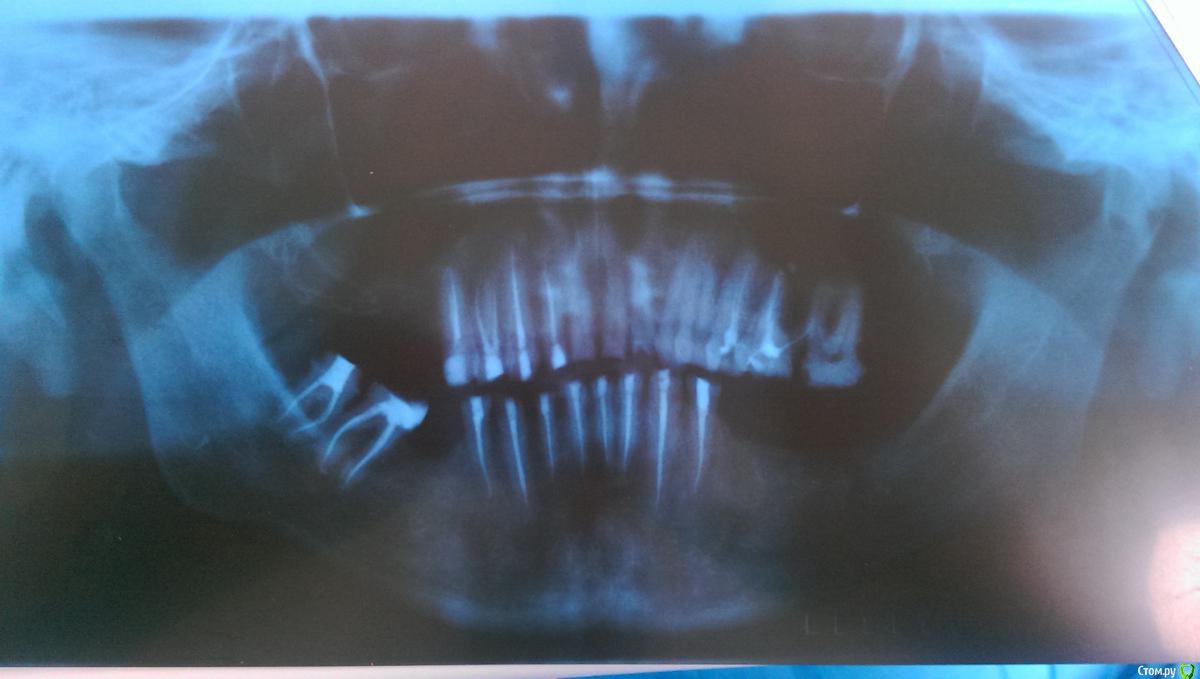

Ром@н Опубликовано 12 мая, 2015 Автор Поделиться Опубликовано 12 мая, 2015 Вот пациент вернулся и даже сделам ОПТГ Ссылка на комментарий

Ром@н Опубликовано 12 мая, 2015 Автор Поделиться Опубликовано 12 мая, 2015 ОПТГ КАЧЕСТВО С ТЕЛЕФОНП Ссылка на комментарий

Петрович Опубликовано 16 мая, 2015 Поделиться Опубликовано 16 мая, 2015 площадь сцепления при фиксации вкладки больше. Ссылка на комментарий

Dr.Berlinale Опубликовано 22 мая, 2015 Поделиться Опубликовано 22 мая, 2015 Судя по снимкам, все должно держаться. Ссылка на комментарий